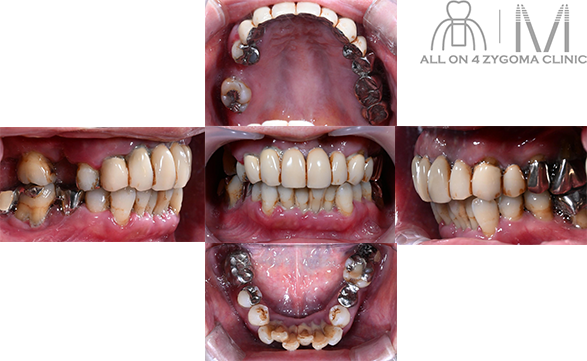

両側上顎は前臼歯歯槽骨に十分なボリュームがないが、頬側に十分なスペースの確保が見込めた。下顎は菲薄な部位はあるものの5┬5を骨整形する事で十分な骨幅の確保が見込めると判断し、この部位に4本ノーマルインプラント埋入予定とした。前歯~小臼歯部で歯槽堤の高低差が大きいことから、安定度を高めるプラットフォームの設計が必要であると考えた。また、頬骨に十分な厚みがある事からザイゴマインプラント4本を用いる上下顎All-on-4治療 を計画した。手術を円滑なものとする為、術中は静脈内鎮静法下での手術を予定した。